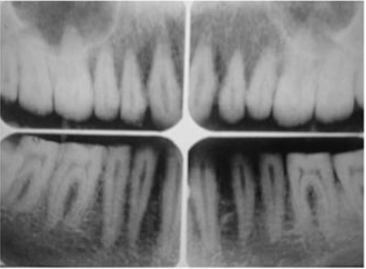

63.下圖之上顎根尖片模糊影像,最可能之原因為:

(A)mA過低 (B)kVp過低 (C)X光片彎曲 (D)病人移動